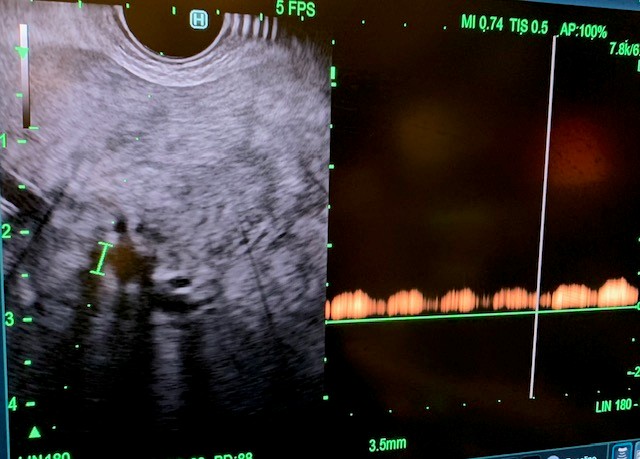

Under general anesthesia, esophagogastroduodenoscopy (EGD) was done using a gastroscope (Olympus America) and there were no esophageal or gastric varices noted. Next, EUS linear array echoendoscope (Olympus America) was passed into the esophagus and advanced into the stomach. The ultrasound image of the liver showed diffuse fatty infiltration. We performed portal pressure gradient using a 25-gauge Cook Echo Tip Insight needle (Cook Endoscopy, Winston Salem, NC). Pulse wave Doppler was used to confirm the middle hepatic vein. From the stomach through the left lobe of the liver, the middle hepatic vein was accessed, and three pressure measurements were taken using digital manometry (Figure 2). The average of 3 measurements from the middle hepatic vein was 17 mmHg. Pulse wave Doppler was used to confirm the left portal vein (Figure 3). Then from the stomach we measured the portal vein pressure by accessing the left portal vein and the average of three measurements was 18 mmHg (Figure 4), giving her a PPG of 1 mmHg. Using Doppler, we ensured there was no bleeding when the needle was withdrawn from both veins (Figure 5 and 6). After the portal pressure gradient measurement, liver core biopsies were done using a 19-gauge Boston Scientific FNB needle (Boston Scientific Marlborough, MA). From the stomach, the left liver lobe was biopsied with the use of EUS to confirm the absence of blood vessels in the needle’s trajectory. One pass and three actuations using the wet heparin technique was performed. The right liver lobe was biopsied from the duodenum and similar methodology was done using the same needle and technique. No bleeding was noted. Both core liver biopsies were sent in formalin to the pathology department for further evaluation.

Figure 2: Middle hepatic vein needle with manometry to obtain hepatic vein pressure accessed via transgastric, transhepatic approach.